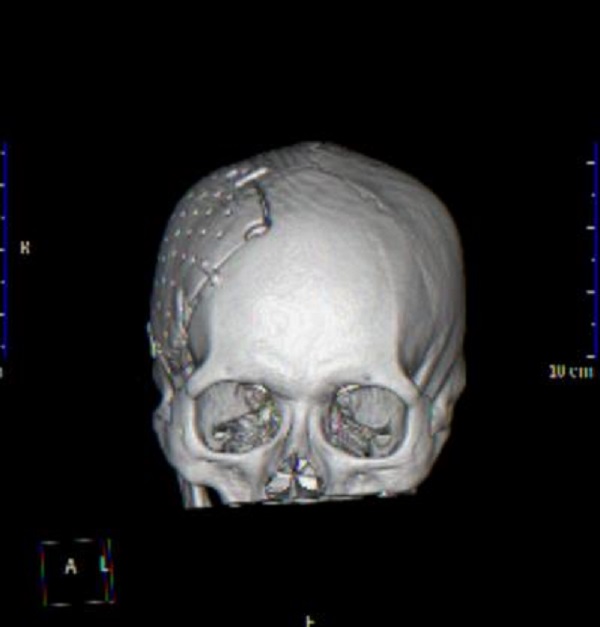

(自体颅骨修补后三维复建图,贴合人体正常生理解剖)